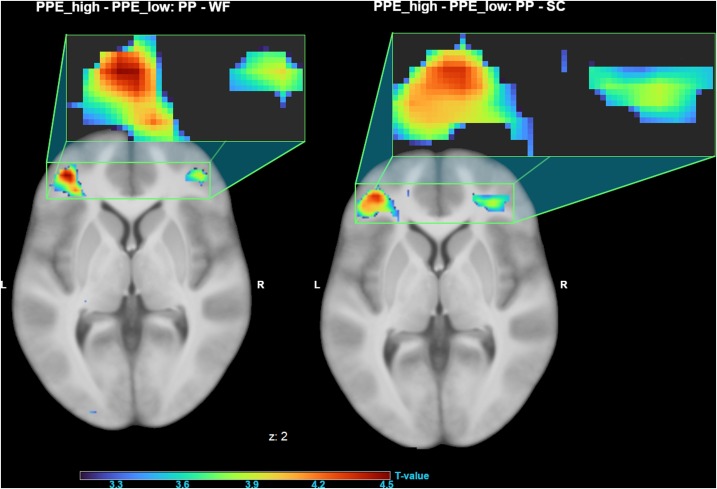

Um estudo de 2021 propôs duas explicações.

O estudo em questão (1) analisou o cérebro de mulheres divididas em dois grupos: aquelas que gostavam desse tipo de vídeo e aquelas que não se interessavam. A análise foi realizada através de imagem por ressonância magnética funcional (fMRI).